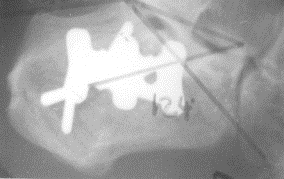

Fig

1. Case 1 Pre op X-Ray |

|

2. Case 1 Post op X-Ray |